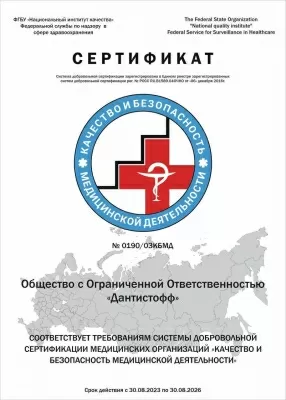

Научная стоматология Дантистофф в Раменках